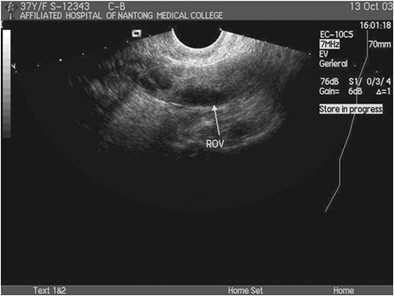

卵巢外形呈扁椭圆形,边界稍有凹凸,中央部为髓质,回声略高。周围区为皮质,回声略低,其内可显示大小不等、边清壁薄的圆形液性暗区为卵泡回声(见图1)。

图1 正常卵巢(箭头所指)